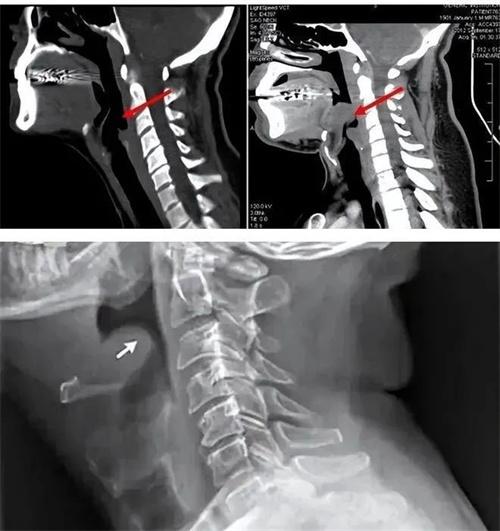

結(jié)合之前的各種癥狀,醫(yī)生通過檢查發(fā)現(xiàn)在會厭處有充血腫脹,將整個聲門部位的堵塞,判斷最終導(dǎo)致這位姑娘死亡的原因是急性會厭炎。人們在進(jìn)食呼吸的時候,空氣會從鼻腔,咽喉進(jìn)入到氣管當(dāng)中,食物從口腔部位進(jìn)入到食管當(dāng)中,會厭就像一個開關(guān)似的,人在進(jìn)食時會向下將喉氣管的入口封閉,呼吸時就向上開放,保證氣流可以順利從氣管中流入。

很多人在吃東西的時候說話都會感覺到被嗆著,這就是會厭沒有能夠及時關(guān)閉而造成的,會厭整體組織結(jié)構(gòu)也是較為疏松的,有炎癥刺激容易有腫脹,受到病毒細(xì)菌的侵犯就可能有較為嚴(yán)重的急性會厭炎產(chǎn)生,使呼吸道這一個入口最終被阻塞。患者就有呼吸困難的情況,較為嚴(yán)重的人在呼吸管這個入口處被完全堵住后,就會使得個人出現(xiàn)窒息。